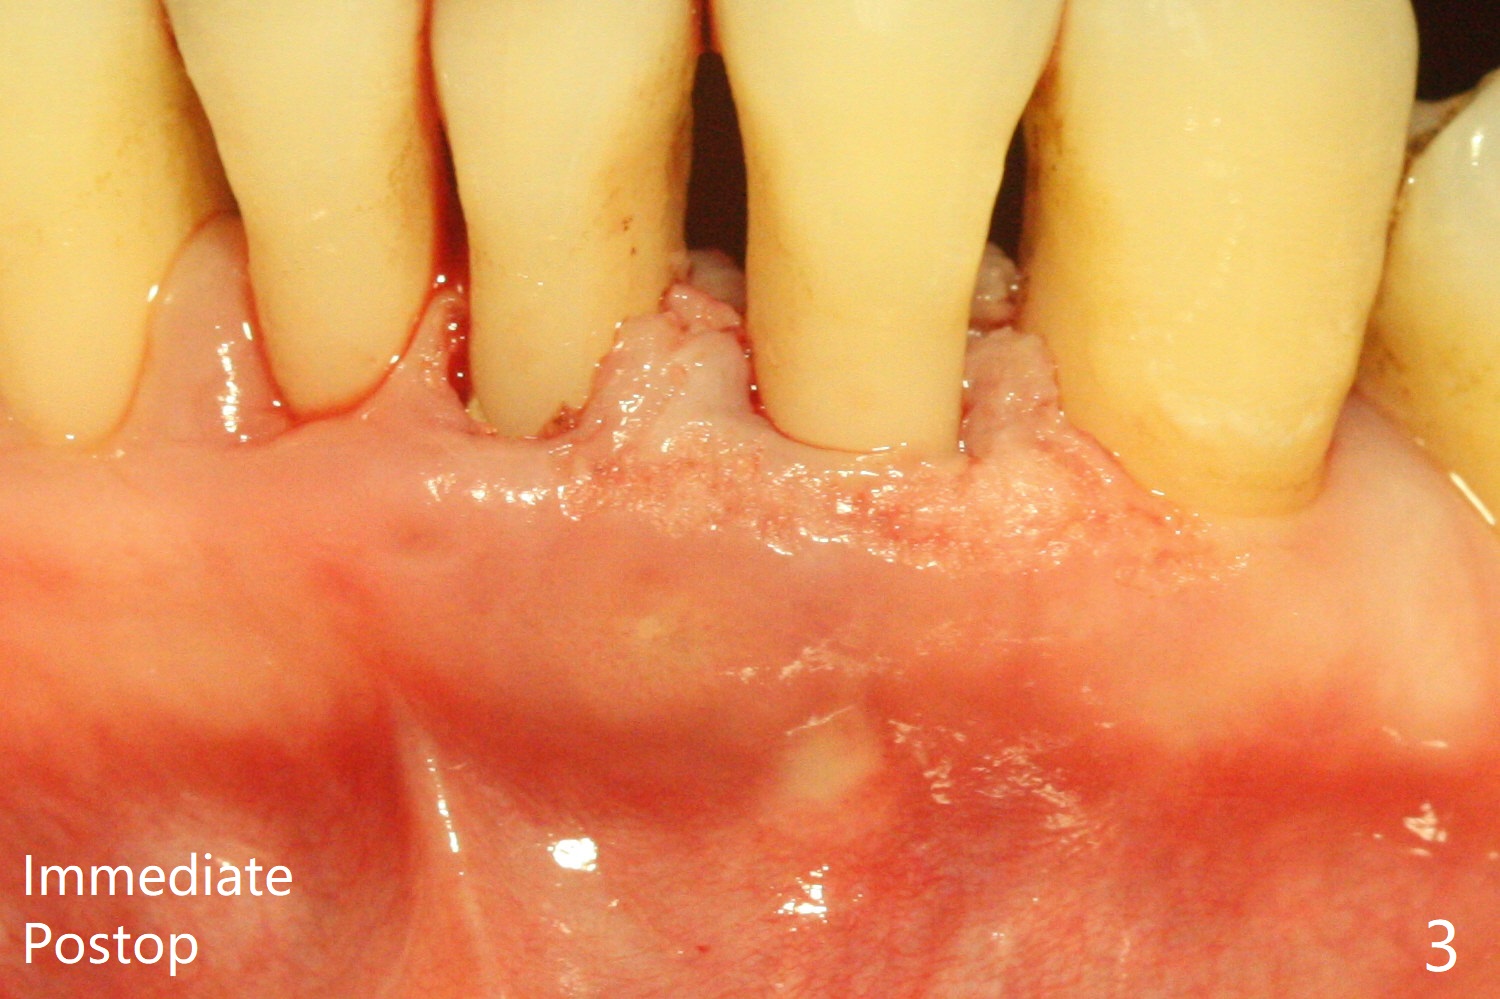

A 45-year-old woman returns for perio maintenance with erythematous and edematous papilla between #23 and 24. Two days later the infection subsides with sinus track (Fig.1 <). With infiltration anesthesia, Waterlase is used for outer and inner (steps 1,3) pocket de-epithelization (and retratction), and sulcular debridement/degranulation (step 5, Fig.3). Gingivectomy (step 2) is omitted because of severe existing gingival recession. Scaling and root planing is not conducted since step 3 seems to be able to remove fine subgingival calculus (Fig.2 <). But it appears not sufficient (Fig.4). Bone decortication should be implemented in future cases (step 6). Mepivacaine is administered in block fashion immediately postop for pain control. The patient is doing fine postop.